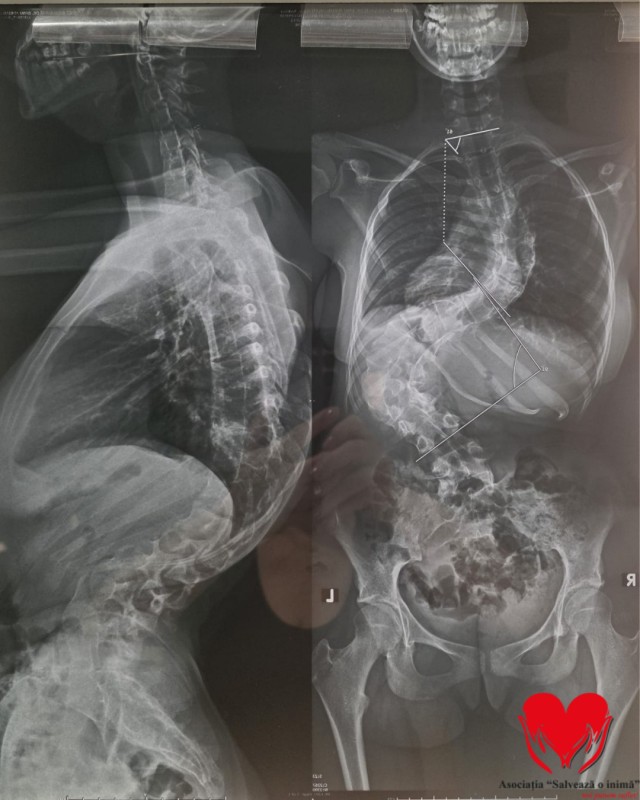

Andreea a fost diagnosticată încă de la o vârstă fragedă cu scolioză. În ciuda tuturor tratamentelor urmate ani la rând – kinetoterapie, fizioterapie, masaj, purtarea corsetului ortopedic și restricții severe – boala a continuat să avanseze. Astăzi, medicii vorbesc despre scolioză severă, cu o curbură de 31 de grade lombar și 61 de grade toracic, valori extrem de periculoase pentru un copil aflat în plină creștere.

Acești ani nu au însemnat doar tratamente medicale, ci și o copilărie pusă pe pauză. Fiecare mișcare este atent controlată, fiecare respirație vine cu efort, iar durerea a devenit o prezență constantă. Mai grav, fără o intervenție chirurgicală urgentă, coloana Andreei riscă să comprime organe vitale, în special plămânii și inima, ceea ce poate duce la pierderea mobilității, insuficiență respiratorie și o viață trăită cu limitări majore.